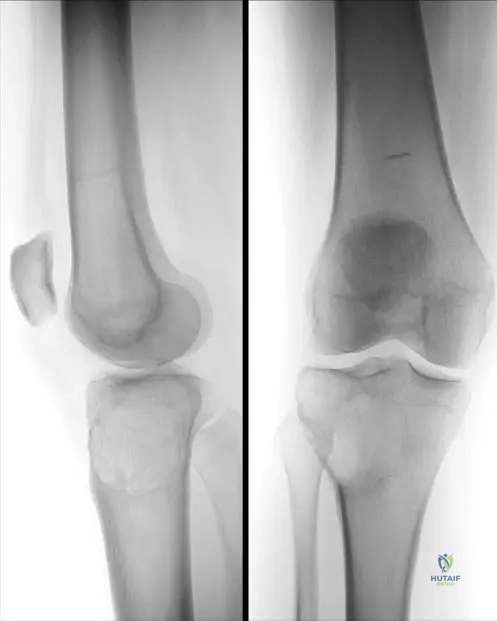

Question 21

A 12-year-old boy presents with multiple palpable bony masses around his knees, shoulders, and wrists. His father and paternal grandfather also have similar bony growths. Physical examination reveals hard, immobile masses protruding from the metaphyses of the long bones, pointing away from the joint. Radiographs confirm multiple osteochondromas (exostoses) arising from the external surface of the bones near the growth plates.

View Answer & Explanation

Correct Answer: C

Rationale: This clinical presentation and family history are classic for Multiple Hereditary Exostoses (MHE), also known as diaphyseal aclasis. MHE is an autosomal dominant disorder caused by inactivating mutations in the EXT1 or EXT2 genes, which encode glycosyltransferases involved in heparan sulfate synthesis. GNAS1 mutations are associated with McCune-Albright syndrome. COL1A1/COL1A2 mutations cause Osteogenesis Imperfecta. FGFR3 mutations cause achondroplasia. TGFB1 mutations cause Camurati-Engelmann disease.

Question 22

A 40-year-old man with a lifelong history of Multiple Hereditary Exostoses (MHE) reports a new, dull ache in his left shoulder, which has been worsening over the past 3 months. He notes that a previously stable exostosis on his scapula has significantly increased in size and is now tender to touch. Physical examination confirms a firm, fixed, tender mass that appears larger than previous assessments.

Rationale: The most serious complication of MHE is malignant transformation of an osteochondroma into a secondary peripheral chondrosarcoma. This risk is estimated to be 1-5% and should be suspected in adults with MHE who develop new pain or rapid growth of a previously stable exostosis, especially in large, axial lesions (e.g., pelvis, scapula). While bursitis can occur, and nerve/vascular compression are possible, the combination of new pain and rapid growth is highly concerning for malignancy and warrants urgent investigation (imaging and potentially biopsy). Pathologic fracture of an exostosis is less common and usually presents with acute pain after trauma.